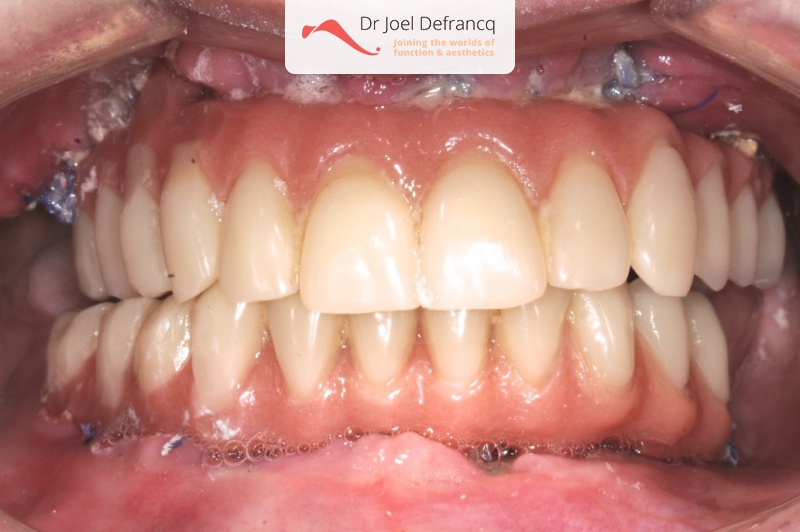

Kait: new teeth in a week - 4 zygoma implants

Behandeling tandheelkundige implantaten

- Vaste tanden op implantaten (bovenkaak)

- Vaste tanden op implantaten (onderkaak)

- Zygoma implantaten